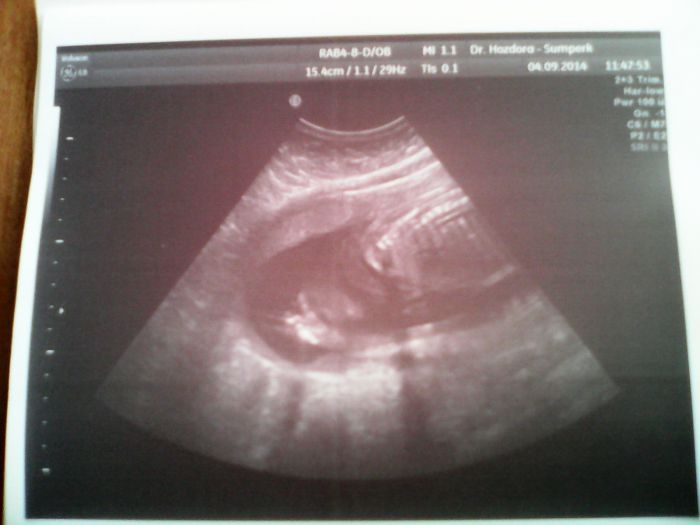

Ahoj holky....dlouho jsem tady nebyla. Zaměstnávali mě koťátka,začátek školního roku i můj oblíbený les. Minulý čtvrtek jsem byla po měsíciv poradně. Mimč měří 26cm a váží 320gr. Pohlavími lékař nebyl schopný říct,i když dělal ultrazvuk přes bříško i spodem. Je to stydlivka. Tak snad to bude zítra lepší na genetickém ultrazvuku. Posílám foto mimča,jak si kryje ručičkou obličejíček

[633543] ahoj Janičko. Tak to je krásná fotecka. Ono to bude asi přece holčička ,když je takle to miminko stydlive ;-). Jsem ráda, že se máte dobře a mimi hezky roste. Na kdy máš vypocitany termín porodu? Tak se hezky opatruj a davej na sebe pozor, ať je vše v pořádku. Posilam pusu Evča :-*